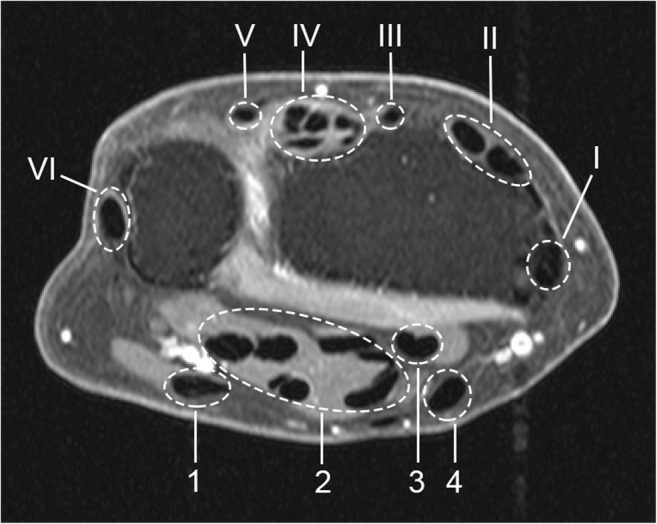

The wrist joint of the most painful side (or the dominant side in cases of equally severe symptoms on both sides) was scanned with a 1.5T extremity MR scanner (GE Healthcare) using a 100-mm coil, with contrast enhancement and frequency-selective fat saturation (T1-Gd). Table 1 summarizes the acquisition parameters. In line with the definitions proposed by Haavardsholm et al [6], tenosynovitis was evaluated in six extensor compartments and four flexor regions within the wrist joint (Fig. 1). Visual scoring was independently performed by two trained readers blinded to clinical data. For each anatomical region, the readers provided a grade on a 0–3 scale based on the estimated maximum width of peritendinous effusion or synovial proliferation with contrast enhancement, as follows: grade 0, normal; grade 1, < 2 mm; grade 2, ≥ 2 mm and < 5 mm; grade 3, ≥ 5 mm. The scoring region was bounded by the distal radius/ulna proximally and the hook of the hamate distally. The intra-reader intra-class correlation coefficients (ICCs) of the two readers for the total tenosynovitis score (sum across all tendon regions), based on 40 MRIs scored twice, were 0.99 and 0.83. The inter-reader ICC for the total tenosynovitis score, based on all 563 MRIs, was 0.87. In what follows, the mean score of the two readers was always considered.

Fig. 1.

Tendon regions (compartments) scored for tenosynovitis, shown on axial MR image of the wrist (T1, post-gadolinium, fat-saturated). The six defined extensor compartments contain abductor pollicis longus, extensor pollicis brevis (I); extensor carpi radialis longus, extensor carpi radialis brevis (II); extensor pollicis longus (III); extensor digitorum communis, extensor indicus proprius (IV); extensor digiti quinti proprius (V); and extensor carpi ulnaris (VI). The four flexor regions contain flexor carpi ulnaris (1); ulnar bursa, including flexor digitorum profundus and superficialis tendon quartets (2); flexor pollicis longus (tendon) in radial bursa (3); and flexor carpi radialis (4). Note: the flexor carpi ulnaris does not have a tenosynovial sheath; nevertheless, inflammation around this tendon is also observed, and therefore, enhancement of tissue surrounding this tendon is scored [11]